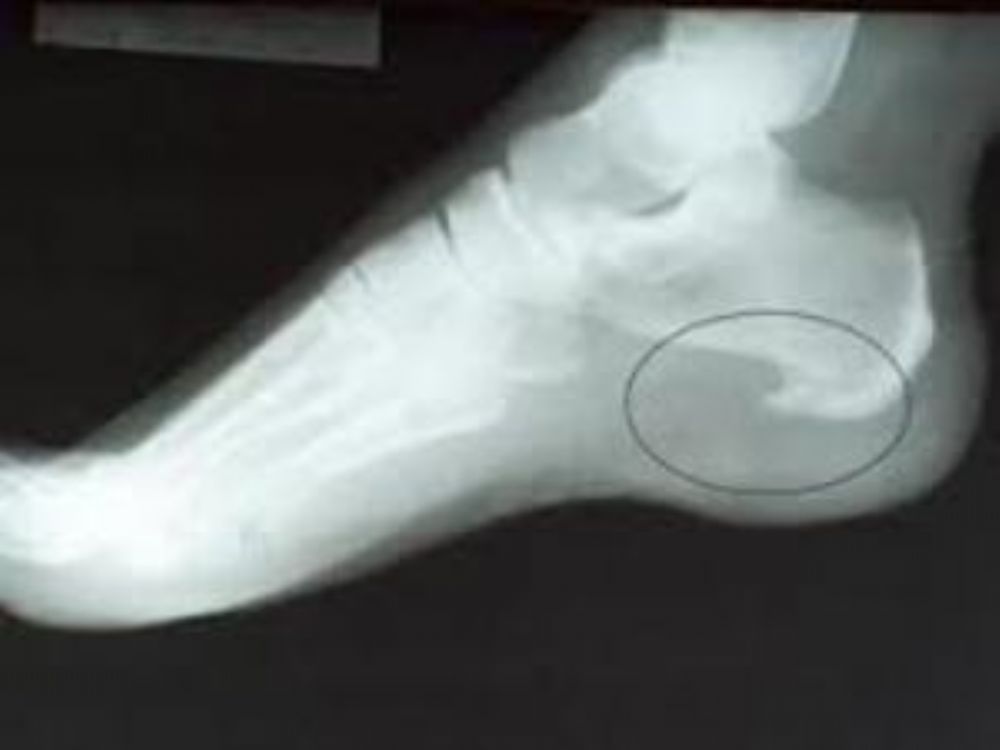

الشوكة العظمية أو مسمار القدم أو كما هو معروف بإسم Calcaneal Heel Spur إشعاعي Radiation